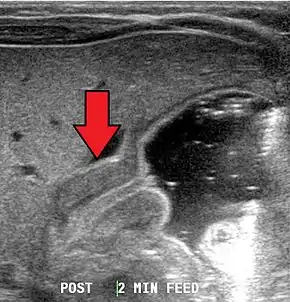

Most cases of pyloric stenosis are diagnosed/confirmed with ultrasound, if available, showing the thickened pylorus and non-passage of gastric contents into the proximal duodenum. Muscle wall thickness 3 millimeters (mm) or greater and pyloric channel length of 15 mm or greater are considered abnormal in infants younger than 30 days. Gastric contents should not be seen passing through the pylorus because if it does, pyloric stenosis should be excluded and other differential diagnoses such as pylorospasm should be considered. The positions of superior mesenteric artery and superior mesenteric vein should be noted because altered positions of these two vessels would be suggestive of intestinal malrotation instead of pyloric stenosis.[7]